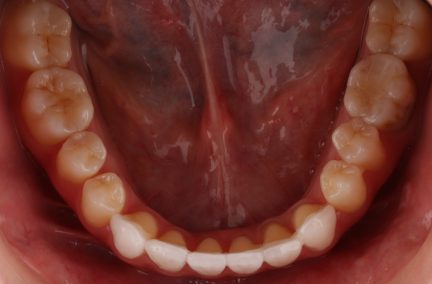

Classe I, morsure bord à bord, espacement, diastème

Facettes

Avec l'aimable autorisation du Dr F. Wang, 2021

État initial